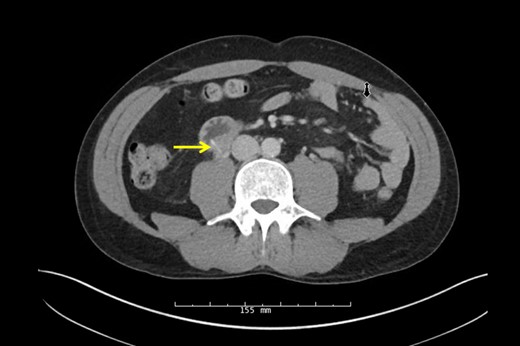

Urology performed a right retrograde pyelogram demonstrating a point of obstruction in the proximal ureter with no contrast extravasation. A guide wire and stent were passed through the obstruction into the hydronephrotic right kidney without difficulty. Following successful stent insertion, fluoroscopy was used to confirm the location of the FB at the junction of the second and third portion of the duodenum. A full Kocher maneuver was performed and the duodenum and ureter were separated. A small, linear, FB was identified projecting from the posterior third portion of the duodenum into the ureter (Fig. 3) and extracted without injury (Fig. 4). The patient's original abdominal pain resolved after the surgery. He was able to tolerate a diet and be discharged on postoperative day 4.

Pathology confirmed a wire metal bristle, likely from a grill brush.